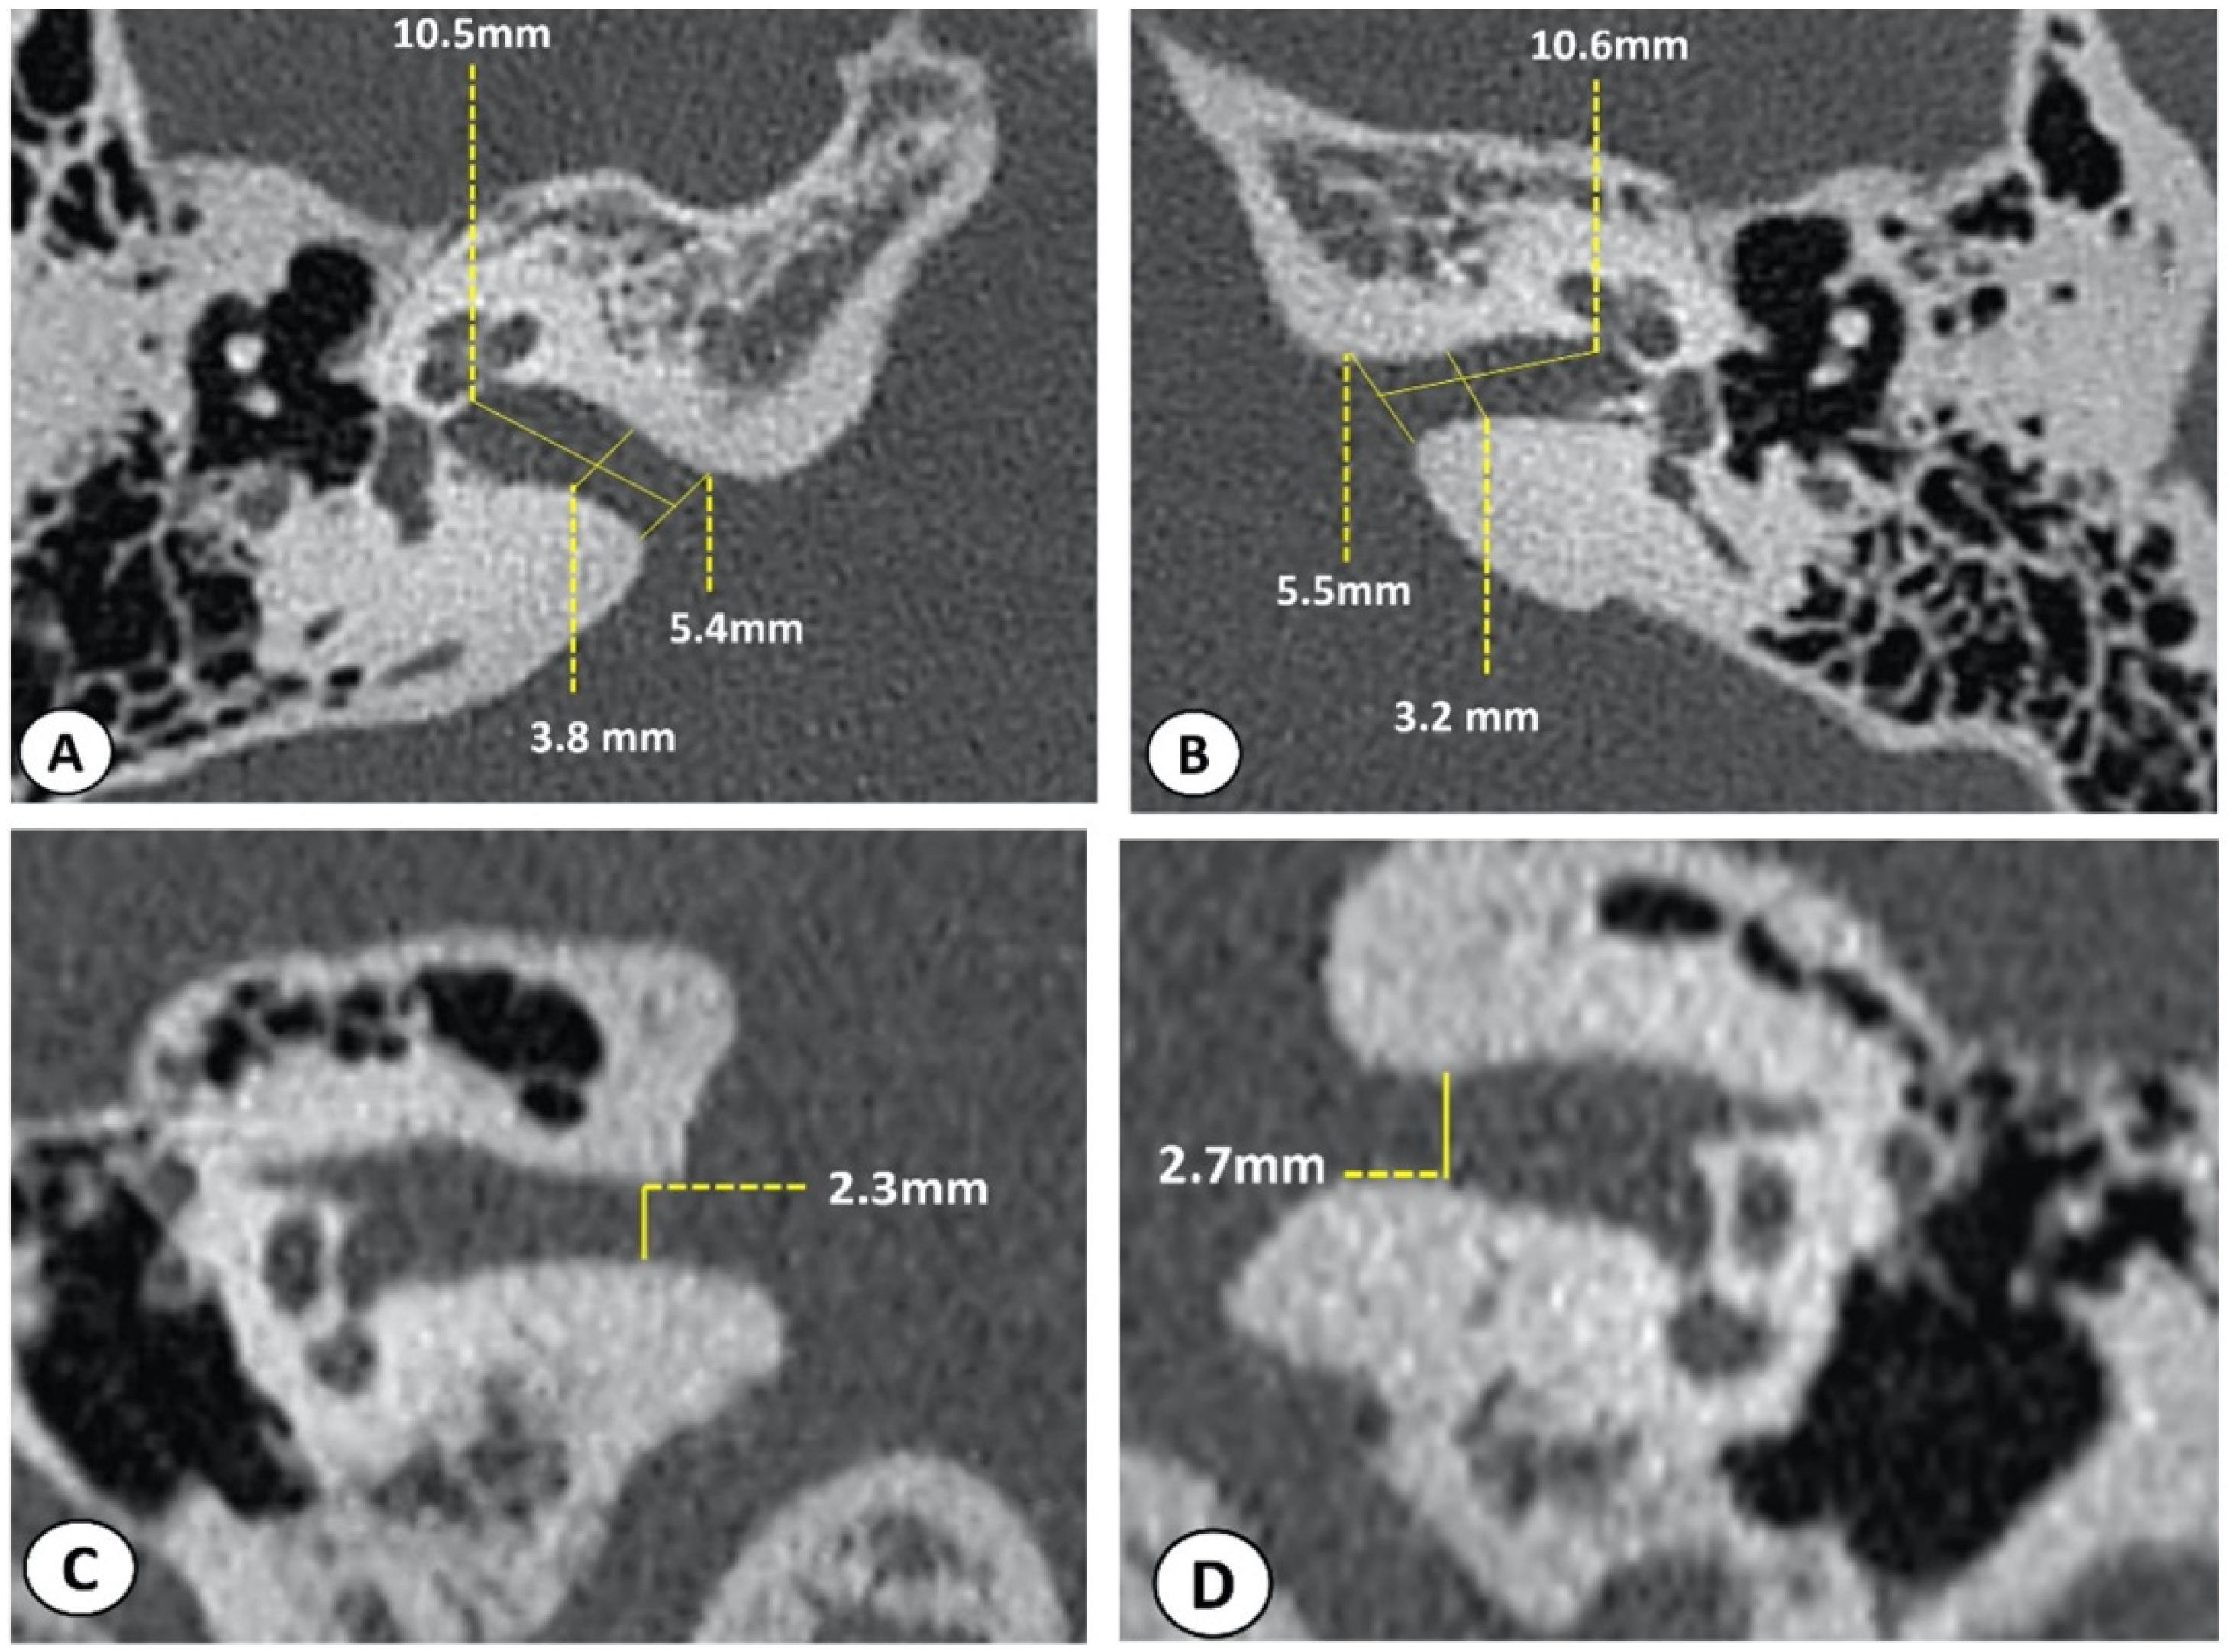

3.3. Radiologic Data

| MRI | CT Scan of Temporal Bones + IAC Measurements (mm) | Conclusion | ||

| Right | Left | |||

| 1 | The internal auditory canals are small in size bilaterally. |

| Bilateral narrowing of the CC caliber of IACs, more marked on the left side. |

| 2 | The internal auditory canals are small in size bilaterally. |

| Bilateral narrowing of the CC caliber of IACs, more marked on the right side. |

| 3 | Bifid aspect of the left saccule. The internal auditory canals are small in size bilaterally. |

| Right narowing of the CC caliber of the IACs. |

| 4 | The internal auditory canals are small in size bilaterally. |

| Bilateral narrowing of the CC caliber of the IACs. |

| 5 | Narrowing of the IAC in their CC caliber more marked on the right. |

| Bilateral narrowing of the CC caliber of the IACs, more marked on the right side. |

| 6 | The internal auditory canals are small in size bilaterally. |

| 7 | Bilateral IAC narrowing |

| 8 | The internal auditory canals are small in size bilaterally. |

| Bilateral narrowing of the CC caliber of the IACs, more marked on the left side. |